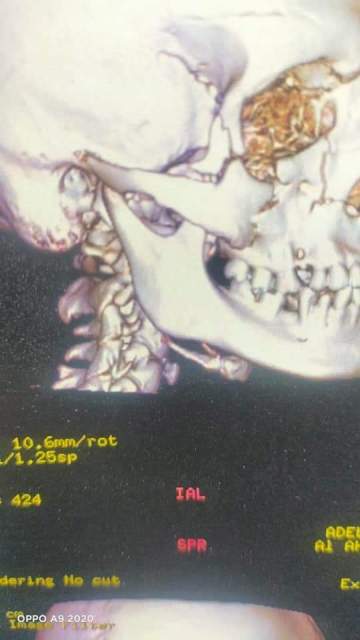

تم إستقبال المريض تحويل داخلى من قسم جراحة المخ والأعصاب إثر حادث وحجزه بقسم جراحة الوجه والفكين، وبعد استكمال العلاج لديهم ، حيث كان يعانى من كسور متعددة بالعظم الوجنى الأيمن بالوجه وبعد عمل الفحوصات الطبية اللازمة والعروض تم إجراء جراحة تحت تاثير المخدر العام لرد وتثبيت الكسور بواسطة الشرائح المعدنية والمسامير ، وخروج المريض تحسن ومتابعة الحالة بالعيادة الخارجية للقسم.

تكون الفريق الجراحى أ.د ثروت عبد الظاهر زميل تعليمى ورئيس القسم ود. مجدى زكى أستشارى جراحة الوجه والفكين ود. أحمد صالح أخصائي جراحة الوجه والفكين ود. جورج لطفى نائب جراحة الوجه والفكين و. عبد المتعال السيد نائب جراحة الوجه والفكين